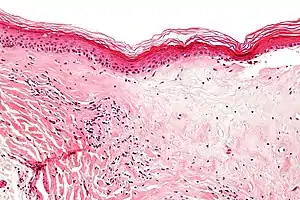

| Micrograph of lichen sclerosus showing the characteristic subepithelial sclerosus (right/bottom of image). H&E stain. | |

A biopsy of the affected skin can be done to confirm diagnosis. When a biopsy is done, hyperkeratosis, atrophic epidermis, sclerosis of dermis and lymphocyte activity in dermis are histological findings associated with LS.[24] The biopsies are also checked for signs of dysplasia.[25]